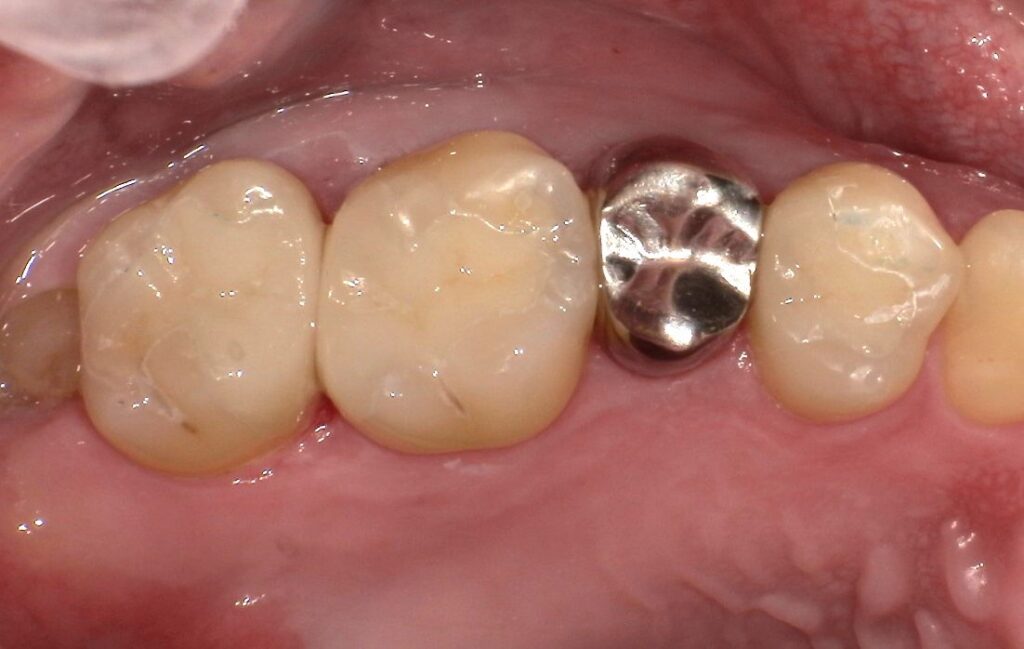

Case.02

治療前

治療後

| 主訴 | むし歯で歯が欠けてしまった。 |

| 治療期間 | 約6ヶ月 |

| 治療費 | 約¥100,000(被せ物代別) |

| 治療内容 | むし歯により抜歯となった部位(右上奥歯)に親知らずを移植。 |

| 治療のリスク | 移植歯がうまく定着しない可能性があります。また、長期的には△。 |